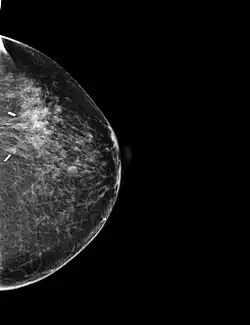

Se trata de la mejora de la imagen considerando los métodos de procesamiento que se basan solo en la intensidad de píxeles individuales. En lo que sigue llamaremos r y s a la intensidad de los píxeles antes y después del procesado. A continuación se presentan ejemplos de tratamiento de imagen por procesamiento de punto utilizando el software de acceso libre ImageJ:

A partir de la opción "Calibrate" del ImageJ , diseño la función de transformación siguiente que me permite incrementar el contraste de la imagen original.